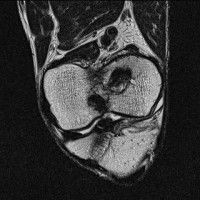

무릎 mri 간단히 봐주실 수 있으시나요 ㅠㅠ

안녕하세요 8년전 십자인대 수술하고 최근 무리한 운동에 무릎 불편감이 생겨서

mri 찍었습니다.

진단결과는 첫 찍은 병원에서 활액막염 이라는 진단을 받았습니다. 혹시 봐주실 수 있으실까요?

올라온 MRI가 단편적이라서 정확한 진단에 어려움이 있지만 십자인대에는 큰 이상이 있지는 않은것 같으며, 무릎관절내 물이 있는 것으로 보아 활액막염의 진단이 맞을 것 같습니다.

하지만 단편적인 영상이기 때문에 촬영병원에서 정확한 판독지 등을 받으시는 것이 좋겠습니다.